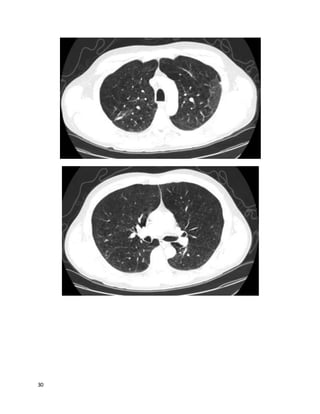

This 78 year old white woman has been coughing for "a good while"; you estimate

at least many months by her history. She is persistently fatigued, has lost 5 pounds,

but has no fevers or night sweats. She is a never-smoker. She sometimes coughs up

blood-streaked sputum. She lives in a high-rise retirement home. Other cuts of her

chest CT are similar to the one below, correlating well with the findings on chest

This is a mycobacterium avium complex infection, with Lady Windemere

syndrome (bronchiectasis and multiple small nodules often involving the right

middle lobe or lingula in nonsmoking elderly women, often with chest wall or

skeletal deformities). The other options are possible but the pattern on imaging

along with the history are most suggestive of MAC, an endemic organism inhaled

5

from soil or water. Her bronchiectasis could perpetuate her cough and hemoptysis;

however, she also has many nodules that are indicative of ongoing infection as the

primary process.Nontuberculous mycobacteria (NTM) also include M. kansasii,

rapidly growing mycobacteria (RGM), and numerous less common species.

Nonpathogenic airway colonization by these organisms is frequently incidentally

discovered and must be differentiated from infection. NTM infection commonly

causes a TB-like pattern (upper lobe cavitary disease); hypersensitivity

pneumonitis (ground glass and centrilobular nodules, sometimes with a mosaic

pattern), or the pattern seen here (nodular bronchiectasis with or without

fibrocavitary disease), along with low-grade nonspecific symptoms usually

including cough and fatigue.